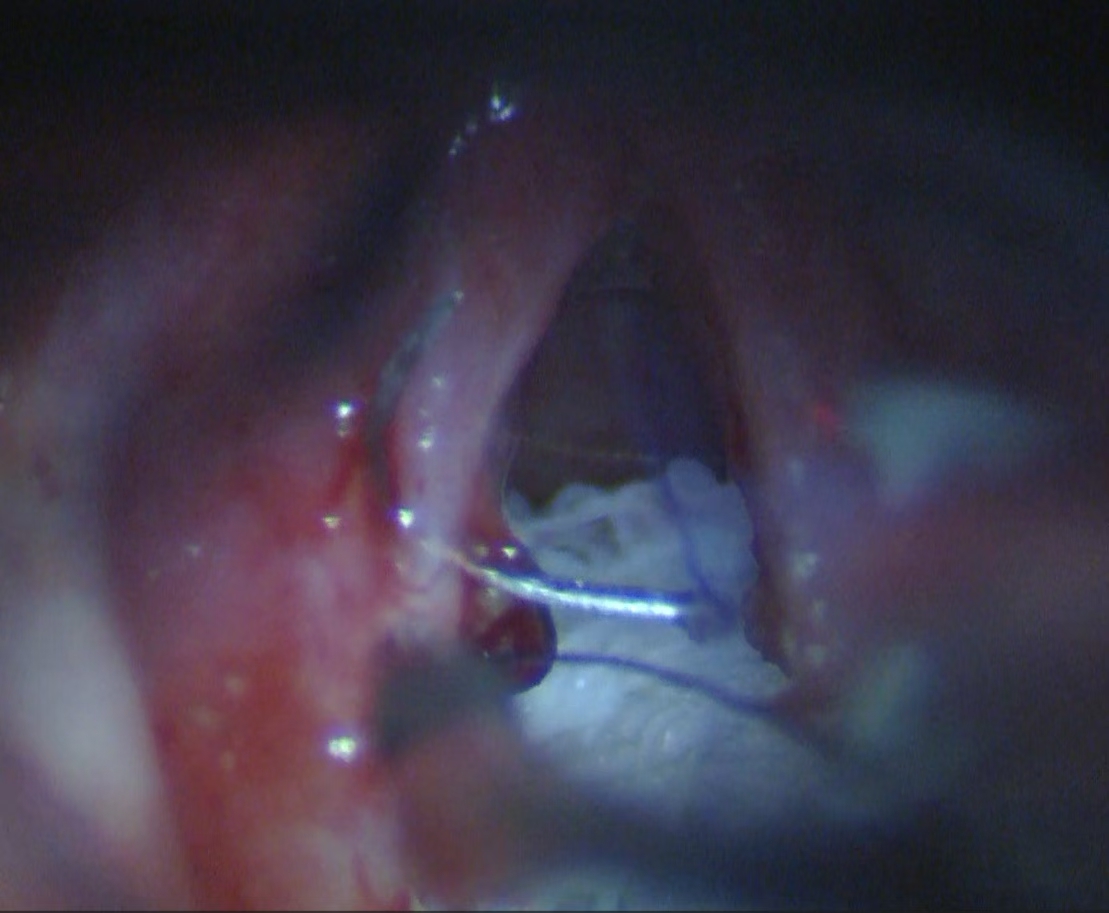

声带疾病(含咽喉早癌)的显微微创手术

由王刘倩医师团队牵头,该团队擅长使用显微镜辅助技术,对各类声带疾病进行精准的诊疗与手术。

其核心特色在于声带息肉切除术及激光切除血管性瘤或糜烂组织,这些方法能在最大限度保留声带本身结构和功能的情况下,彻底清除病变组织。

在显微缝合技术方面,该团队可精确到毫米级别,手术后患者能快速康复并持续改善发音质量。这种高超技艺使得王刘教授团队成为声带疾病治疗领域的佼佼者。